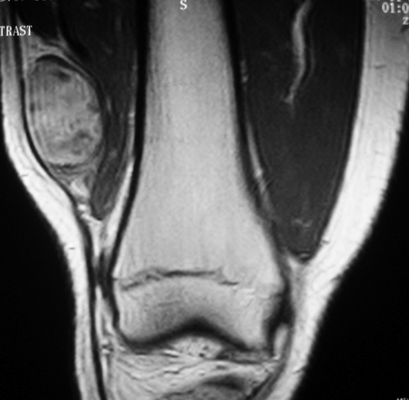

Саркома мягких тканей бедра на МРТ

КТ мягких тканей бедра

Компьютерную томографию бедра проводят при травмах этой области, для оценки состояния сосудистой системы и с целью выявления воспалительных и неопластических процессов. В изучении структуры рыхлых элементов чаще применяют МРТ, которая отличается высокой информативностью и безопасностью. Но в некоторых случаях, например при наличии противопоказаний, назначают мультиспиральную КТ.

КТ с применением контраста визуализирует сеть сосудов, их проходимость, наличие образований в просвете вен и артерий. Благодаря послойным снимкам можно определить характер кровоснабжения области бедра, увидеть локализацию травматических изменений и новообразований.